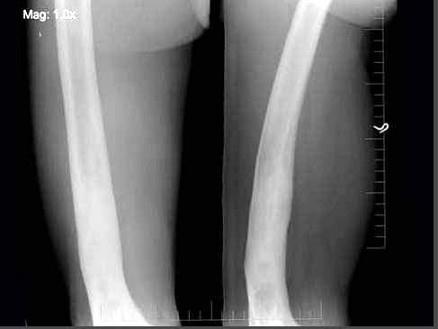

问题 男,58岁,右大腿酸痛,弯曲变形,有外伤史,右股骨摄片如图所示,最可能的诊断是?(?)

选项 A.硬化性骨纤维结构不良 B.慢性化脓性骨髓炎 C.骨质软化症 D.慢性硬化性骨髓炎 E.以上均不正确

答案 B